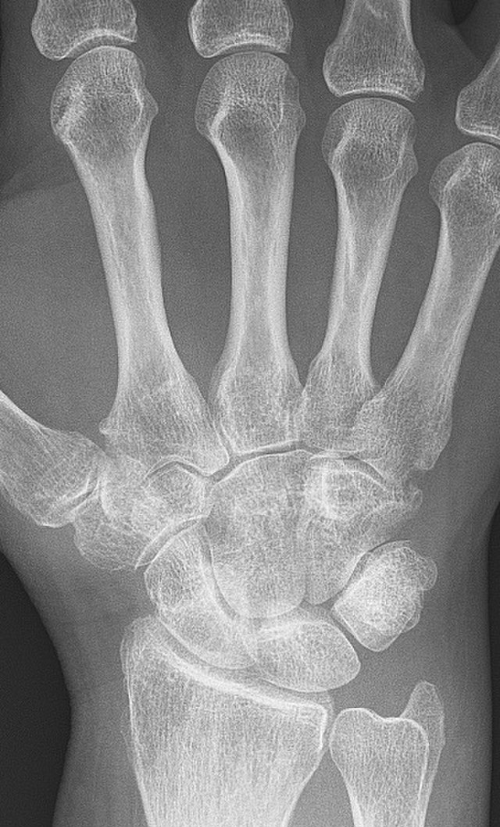

류마티스 관절염은 초기증상 특징을 잘 알고 빠르게 대처해야 합니다. 류마티스 관절염의 진단은 위에 언급한 류마티스 초기증상이 나타났는지 여부와 류마티스 인자의 혈액 검사, X레이 검사를 통해 진행됩니다.